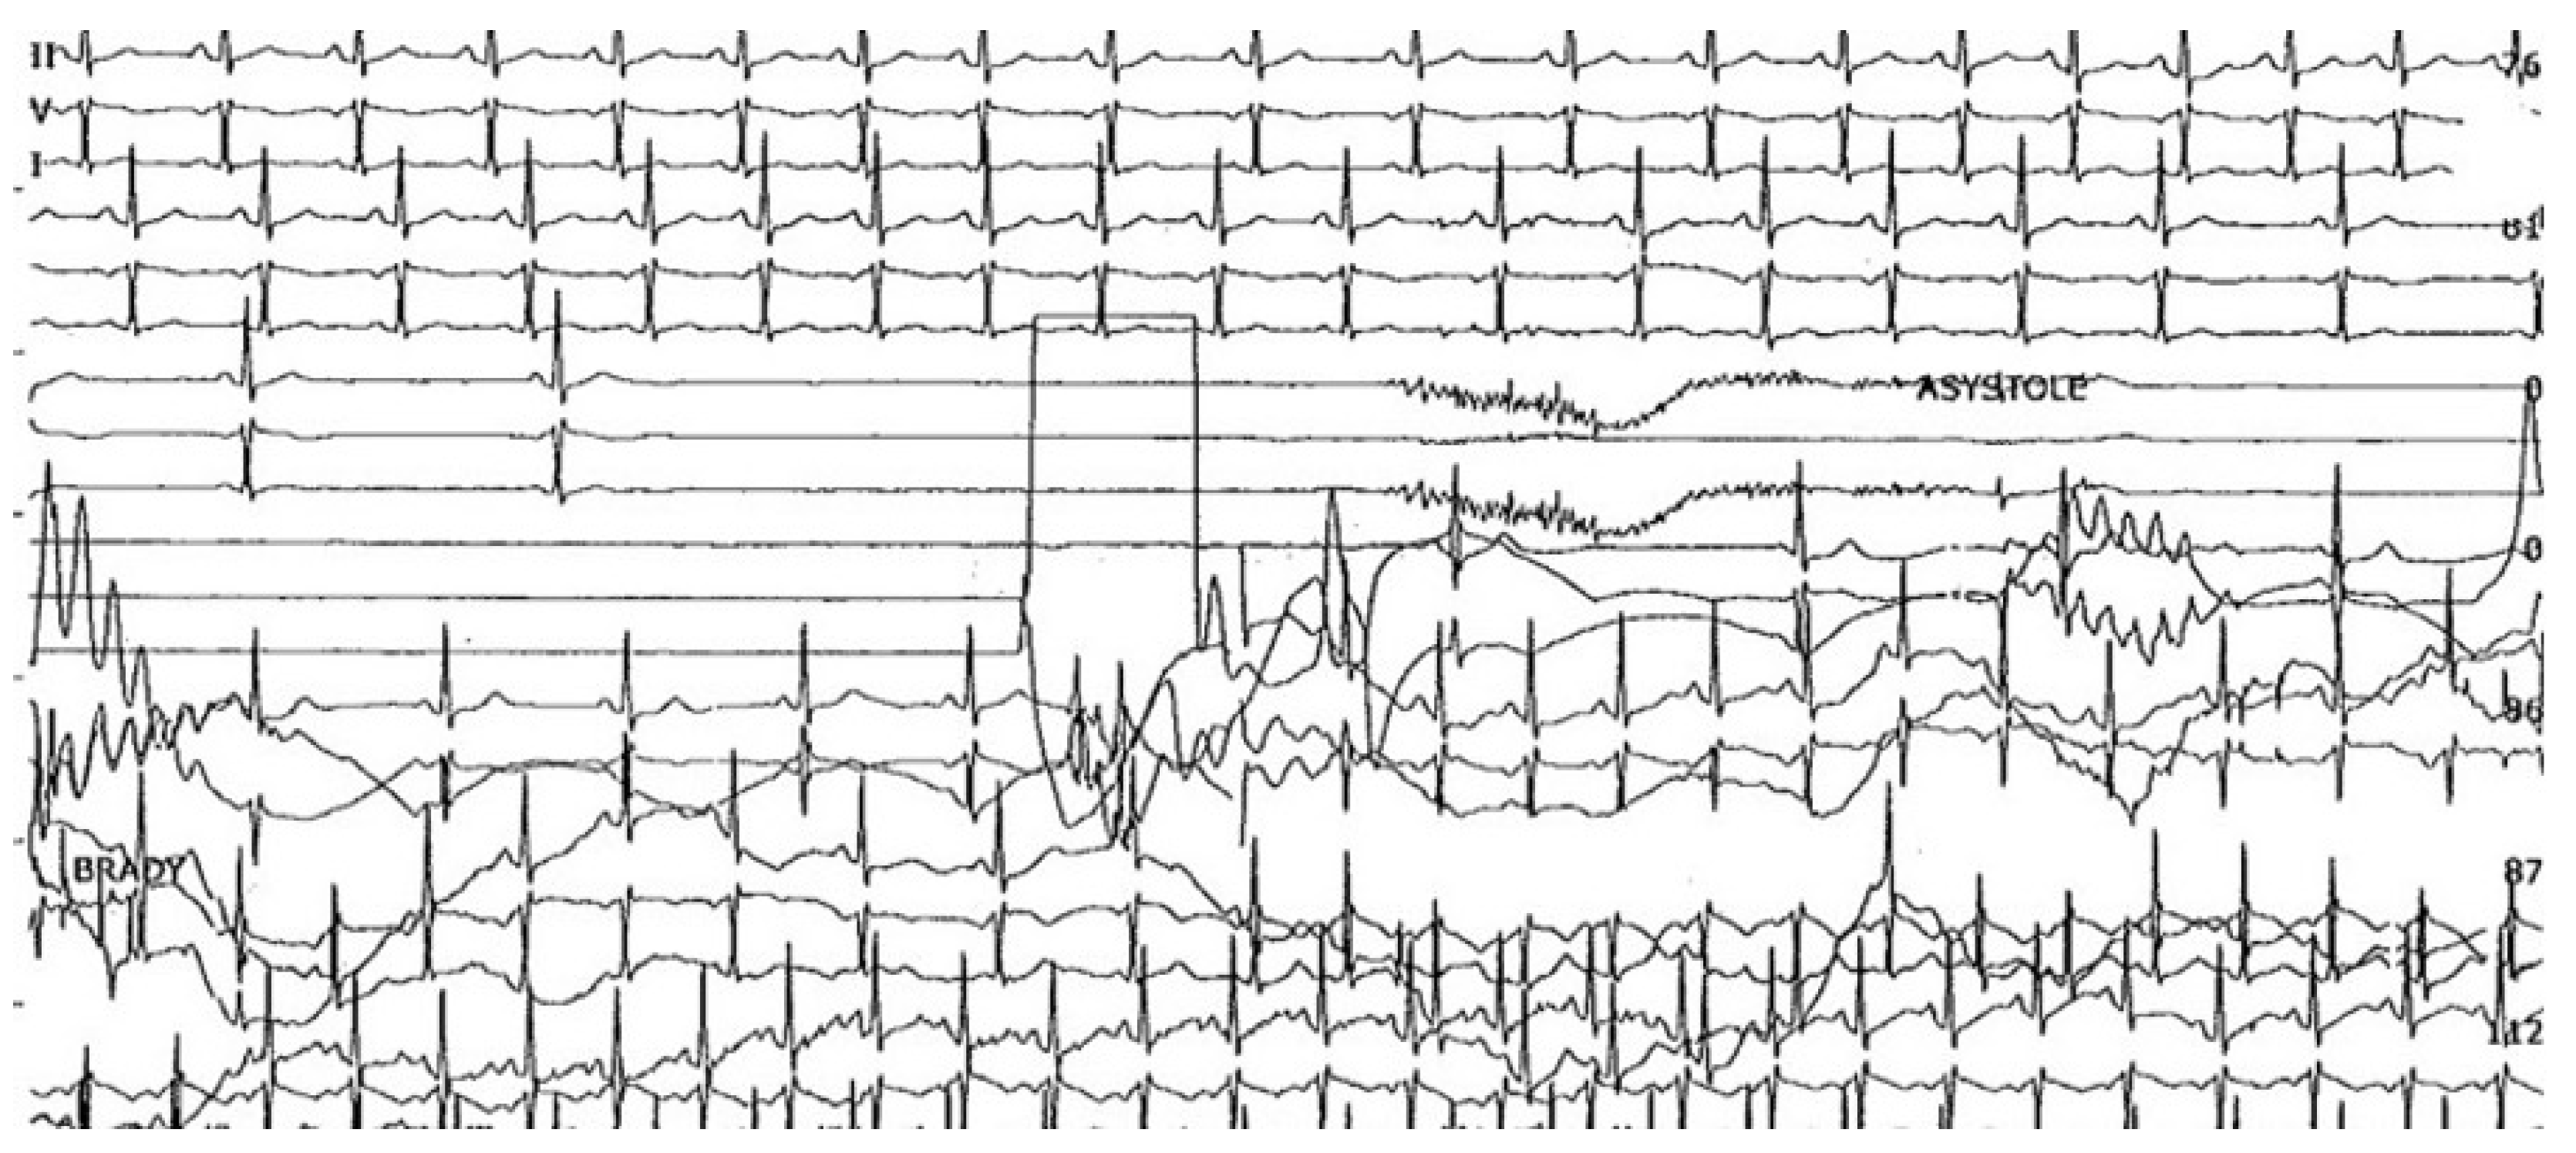

3. Cardioinhibitory Response

- Brignole, M. Different electrocardiographic manifestations of the cardioinhibitory vasovagal reflex. Europace 2009, 11, 144–146. [Google Scholar] [CrossRef] [PubMed]

- Zysko, D.; Gajek, J.; Kozluk, E.; Mazurek, W. Electrocardiographic characteristics of atrioventricular block induced by tilt testing. Europace 2009, 11, 225–230. [Google Scholar] [CrossRef] [PubMed]

- Chou, H.H.; Lin, K.H.; Luqman, N.; Kuo, C.T. Prolonged ventricular asystole, sinus arrest, and paroxysmal atrial flutter-fibrillation: An uncommon presentation of vasovagal syncope. Pacing Clin. Electrophysiol. 2003, 26, 914–917. [Google Scholar] [CrossRef]